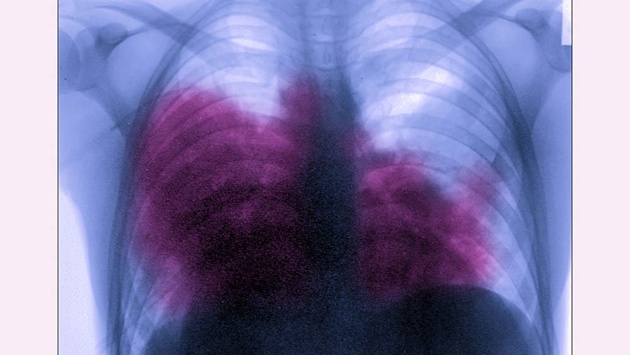

Легионеллез - это острое инфекционное заболевание, обусловленное различными видами микроорганизмов, относящихся к роду Legionella. Заболевание протекает, как правило, с выраженной лихорадкой, общей интоксикацией, поражением легких, центральной нервной системы и органов пищеварения.